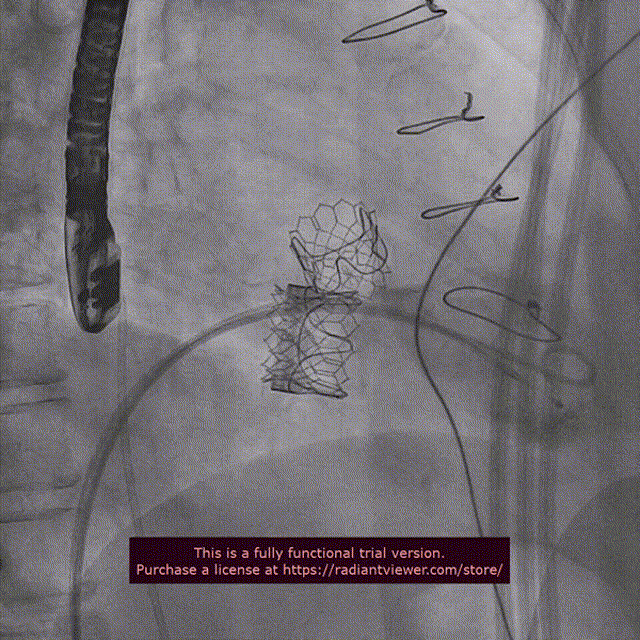

近日,中国医学科学院阜外医院潘湘斌教授团队,在多科室的通力配合下,凭借扎实的手术功底顺利完成一例经导管主动脉瓣和二尖瓣瓣中瓣置换术。

手术过程